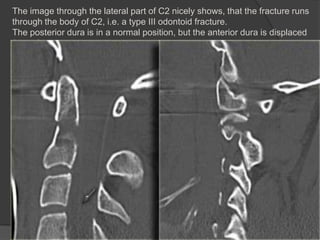

The image through the lateral part of C2 nicely shows, that the fracture runs

through the body of C2, i.e. a type III odontoid fracture.

The posterior dura is in a normal position, but the anterior dura is displaced

(arrow).

The image throughthe lateral part of C2 nicely shows, that the fracture runs through the body of C2, i.e. a type III odontoid fracture. The posterior dura is in a normal position, but the anterior dura is displaced (arrow).